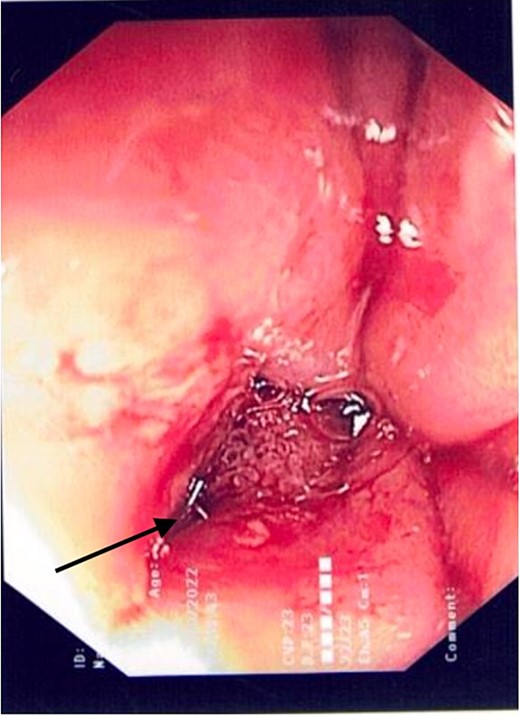

A 21 year old male presented to the emergency department with 1 day of abdominal pain and vomiting. Seven days earlier, a laparoscopic Nissen fundoplication, posterior cardiopexy, and anterior gastropexy for reflux aspiration were performed. Medical history included a left branchial cyst and asthma. Gastroscopy 3 years prior demonstrated reflux oesophagitis and small hiatus hernia, with no previous surgeries. On examination, blood pressure was 118/85 mmHg, with tachypnoea to 40 breaths per minute and tachycardia to 121 beats per minute. He was peritonitic. Laboratory results demonstrated C-reactive proteinof 543 mg/dL and Lactate of 5.9 mmol/L. He was commenced on intravenous fluid resuscitation and piperacillin-tazobactam. Computed tomography (CT) abdomen demonstrated large amounts of intra-abdominal free fluid, and more than expected pneumoperitoneum for laparoscopy performed 7 days prior, as seen in Fig. 1. Nasogastric tube (NGT) and indwelling urinary catheter were inserted, and the patient was organized for a damage control diagnostic laparoscopy +/− laparotomy.

Non-contrast CT abdomen/pelvis in axial view demonstrating diffuse intra-abdominal free fluid with multiple large locules of intraperitoneal free air.